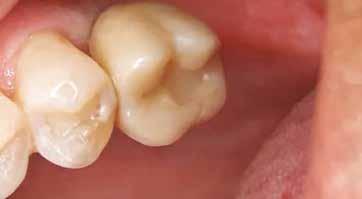

16. ábra: Klinikai kép az implantátumok körüli lágyszövetről a végleges pótlásátadás után. – 17. ábra: Klinikai kép az implantátumok körüli lágyszövetről egy évvel az átadást követően. – 18. ábra: Klinikai kép az implantátumok körüli lágyszövetről két évvel az átadást követően. – 19. ábra: Klinikai kép az implantátumok körüli lágyszövetről öt évvel az átadást követően.

A páciens mobilis implantátum körüli lágyszövettel rendelkezett, a keratinizált íny szélessége kevesebb volt, mint 1 mm és a nyálkahártya vastagsága nem érte el a 2 mm-t. Az ínyszél az implantátum platform vonalában volt. Az alábbi műtéti technikával jelentős javulást sikerült elérnünk az implantátum körüli lágyszövetek minőségében és a nem elmozduló keratinizált szövet szélesedett 4 mm-rel. A Kígyótechnikánál alkalmazott elforgatott lebeny a szabad keratinizált íny lebeny előnyeivel növeli a nem elmozduló nyálkahártya szélességét az implantátum körül. Biztosítja továbbá a jó vérellátást és a nyeles lebeny stabilitását, ami kisebb mértékű zsugorodást eredményez, mint egy szabad lágyszövet lebenyátültetésnél (29).